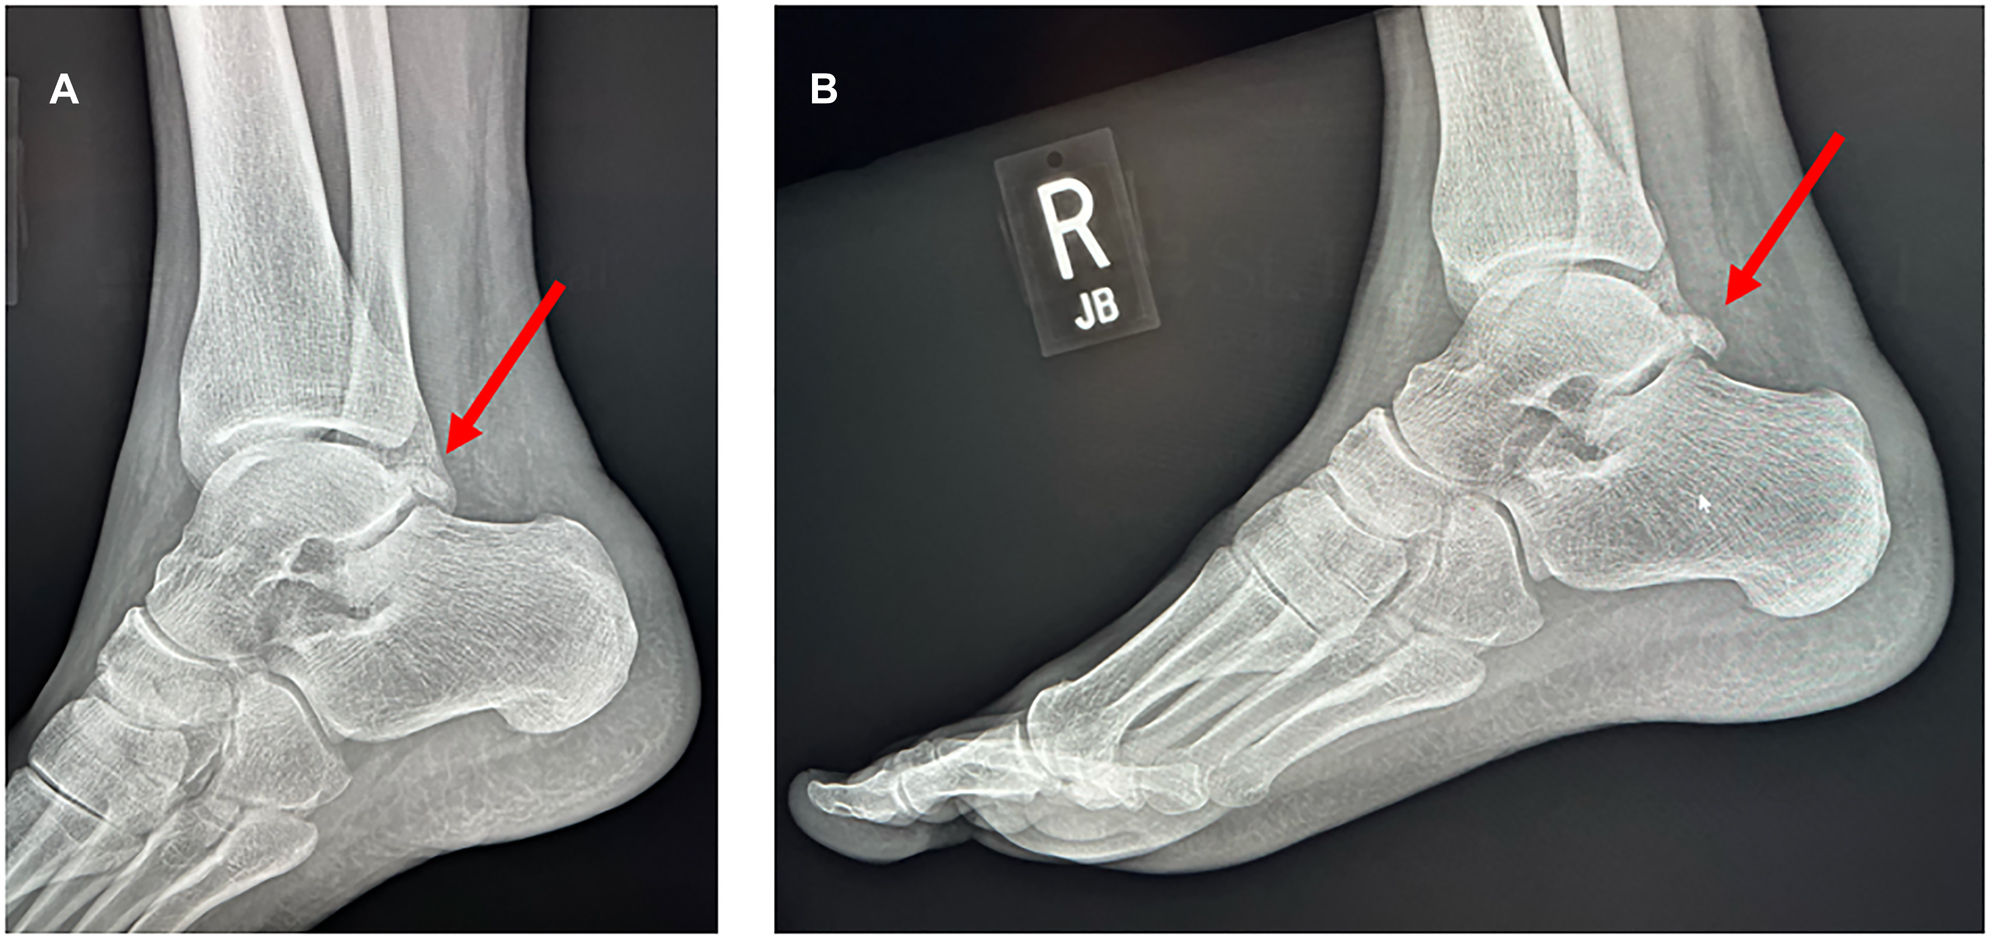

A 47-year-old man presented to the Emergency Department in November 2021 with right foot pain and difficulty walking. The patient had undergone trauma to the right ankle after a cut tree trunk snapped back and hit his posterior heel. He presented the next day after developing mild pain in the right lateral midfoot and pain with ambulation. He had full range of motion of the ankle and foot without difficulty. There were no open wounds. There was no tenderness to palpation over the Achilles tendon, and the patient was able to fully dorsiflex and plantarflex the foot. There was some mild tenderness to palpation in the proximal, dorsal midfoot with mild associated swelling. The patient had no prior history of injuries or pain in the ankle. Oblique and lateral right ankle X-rays were obtained and demonstrated the accessory bone (Figure 1), and the patient was diagnosed with an os trigonum.

(A) X-ray of the patient’s right ankle (oblique view). (B) X-ray of the patient’s right ankle (lateral view).